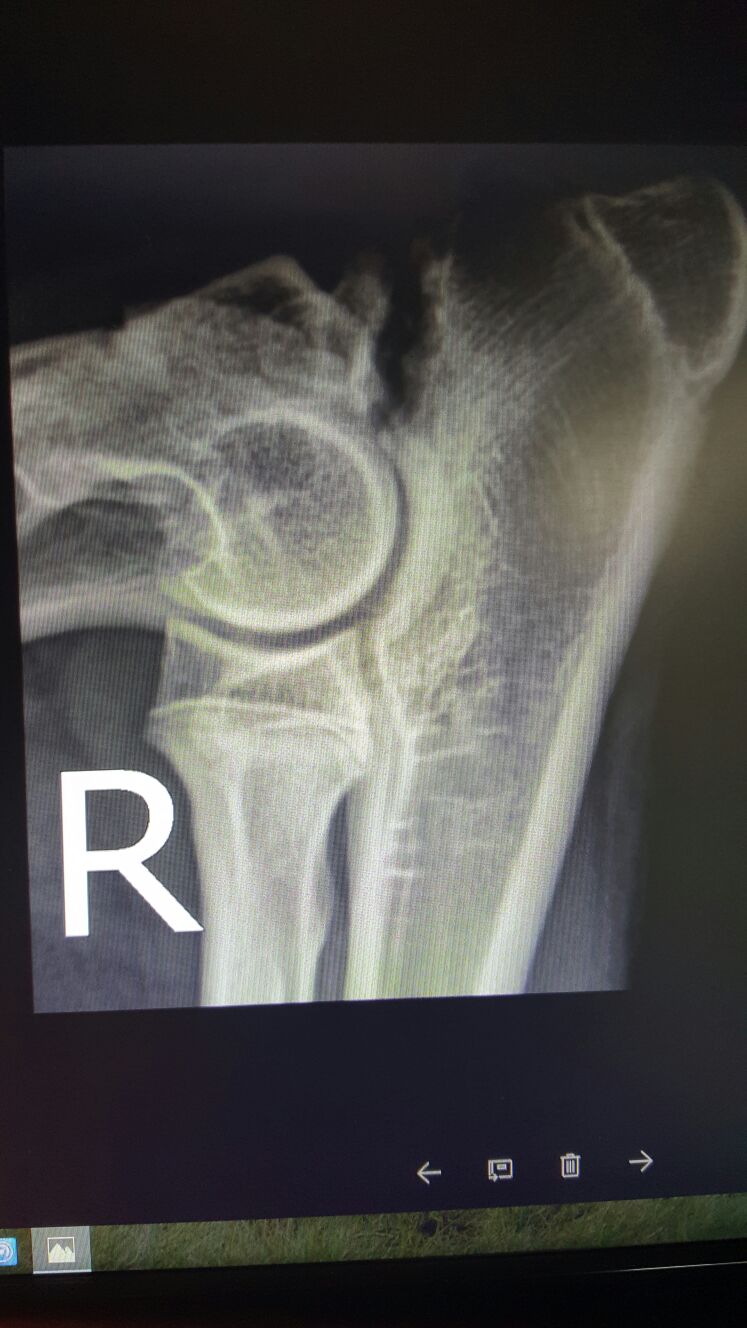

Dobry den, doporucuji otazku smerovat na ortopeda,resp.pracoviste,kde se tyto zakroku provadeji. V Praze napr.doktor Duchek, Vetcentrum, velmi vysokou uroven osetreni nabizi klinika Jaggy. Bude urcite nutne poridit vice sbimku, i druhe, predpokladam zdrave, koncetiny, obou kycli a komplexni vysetreni pacienta pro co nejpresnejsi posouzeni pripadu.